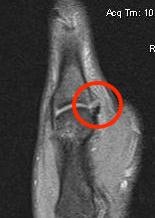

B. Displaced UCL

Coronal MRI demonstrating displaced distal UCL avulsion